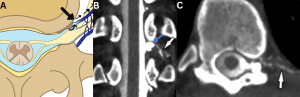

Fig 13: Figure A: Illustration demonstrating a spinal ventral dural tear caused by a calcified discal spur (straight black arrow). Black curved arrows indicate the route of cerebrospinal fluid (CSF) leakage into the epidural space.

Figure B: Sagittal bone-window CT image of the thoracic spine showing a discogenic spur (red arrow).

Figure C: Sagittal T2-weighted MR image of the thoracic spine demonstrating a T2 hyperintense anterior spinal epidural collection (SLEC) (green arrow).